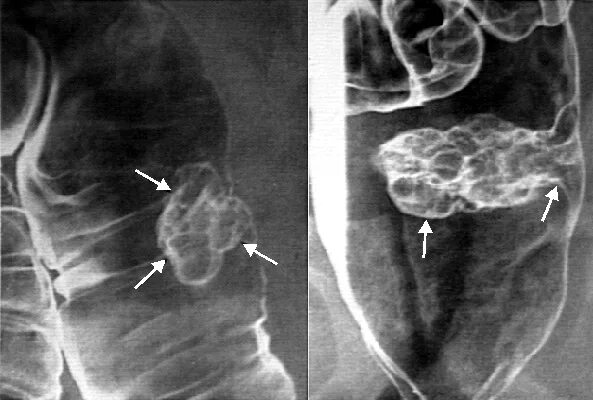

Диффузный семейный полипоз